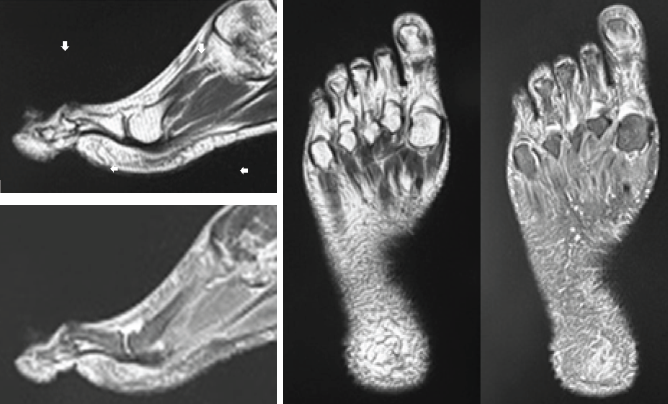

The condition was distinct from the so-called claw toe or hammer toe. Mild resistance to passive motion was observed; however, firm downward pressure temporarily achieved a plantar flexed position. There were no neurological abnormalities observed that are typically associated with schizophrenia or spinal cord disorders. The patient’s Japanese Society for Surgery of the Foot (JSSF) hallux metatarsophalangeal (MTP)-interphalangeal scale was 23. While radiographic findings were consistent with gross observations, the arrows of magnetic resonance imaging (MRI) (T1WI, T2WI) of the right MTP joint indicated areas of high signal intensity (Fig. 2).

Figure 2: Magnetic resonance image of heightened signal intensity at the right metatarsophalangeal joint, indicative of localized tendinitis on the dorsal aspect of the right extensor hallucis longus. The MRI findings revealed that the area of signal intensity alteration was thin and localized along the tendon course at the level of the MTP joint, which ruled out the possibility of tumorous changes. Adhesion of the EHL tendon sheath to the surrounding tissues was considered the most likely cause of the stiffness, suggesting local tendinopathy. No other relevant observations were made. Based on the findings, the patient was clinically diagnosed with the right EHL tendinopathy, which associated with hyperdorsiflexion of the right hallux.